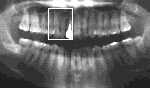

30歳 女性 2」 治療後Dental写真

初診時 パノラマ カリエス治療後の歯髄炎および根尖病巣

「ムシ歯でもないのに歯ぐきが腫れて…」と不安そうな表情。

臼歯部に二次カリエスが認められるものの、清掃状態は比較的良好。歯槽骨の吸収も認められない。 10数年前に2」の治療(CR充填)を受けたのち、同部根尖付近の違和感を感じるものの放置。 数カ月前から歯肉の腫脹と疼痛が著明となり来院。

レントゲン診査の結果、2」の根尖病巣が認められたので、感染根管治療(失即充)を施行。 術後症状は暫時軽減し予後良好。

10数年前の治療後、切削時の発熱、またはCR(残留モノマー)充填の薬物刺激により歯髄が 炎症を起こし、変質(→腐敗)した結果根尖部に炎症が波及したものと思われる。